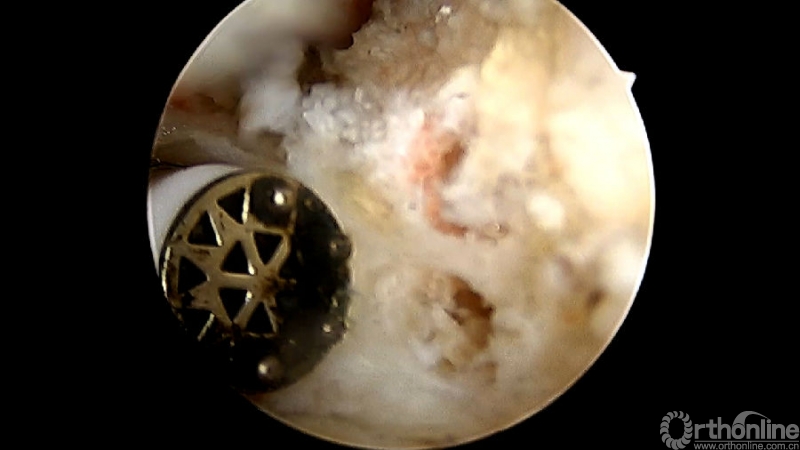

使用磨钻按照范围将下关节突内缘磨薄,然后用骨凿切除下关节突内缘显露出上关节突内缘及关节面。

术中第一次及第二次的两个定位孔